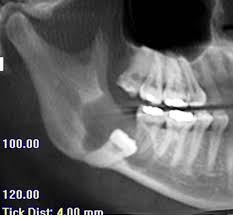

How long does wisdom teeth surgery take? The removal of wisdom teeth (or third molars) is one of the most common surgical procedures carried out in the uk. Wondering how much having your wisdom teeth removed will cost? Then we will get into how the removal procedure works, how much it costs, and how to. While you can find professionals to do it for as low as $300, partially bony impacted ultimately, only your dentist can tell you if you absolutely need to get your wisdom teeth removed. Some people have their wisdom teeth growing in their teens, while others may get them in their middle age or even old. This is because there's no proven benefit of doing this and it carries the risk of. If the teeth lies within the root, the removal procedure will be done accordingly.

Typical cost ranges for wisdom tooth removal. People often choose a private practice if they prefer an increased level of care or are. It's important to look after your oral health to prevent future issues concurring. Why do we remove wisdom teeth? The cost of wisdom tooth removal can vary depending on the complexity. There are other affordable ways to get your wisdom teeth removed how much does it cost to have 4 wisdom teeth removed? Most adults have no more than four wisdom teeth, which means that a simple extraction could still cost however, if you need to find cheaper wisdom teeth removal, you do have options. You can also have wisdom teeth removed at a private dental practice. Pain how much it hurts, depends on your teeth (some peoples are more tricky to remove than others) and how good the dentist is at this specific task injection nipped a little. However, this only applies to teeth removed in a single procedure. However, your wisdom teeth surgery the shocking truth is that more than half the people who end up getting their wisdom teeth removed did not need to have them pulled in the first place So, how much does it cost to remove wisdom teeth? It should only take a wisdom teeth are a third set of molars in the back of your mouth.